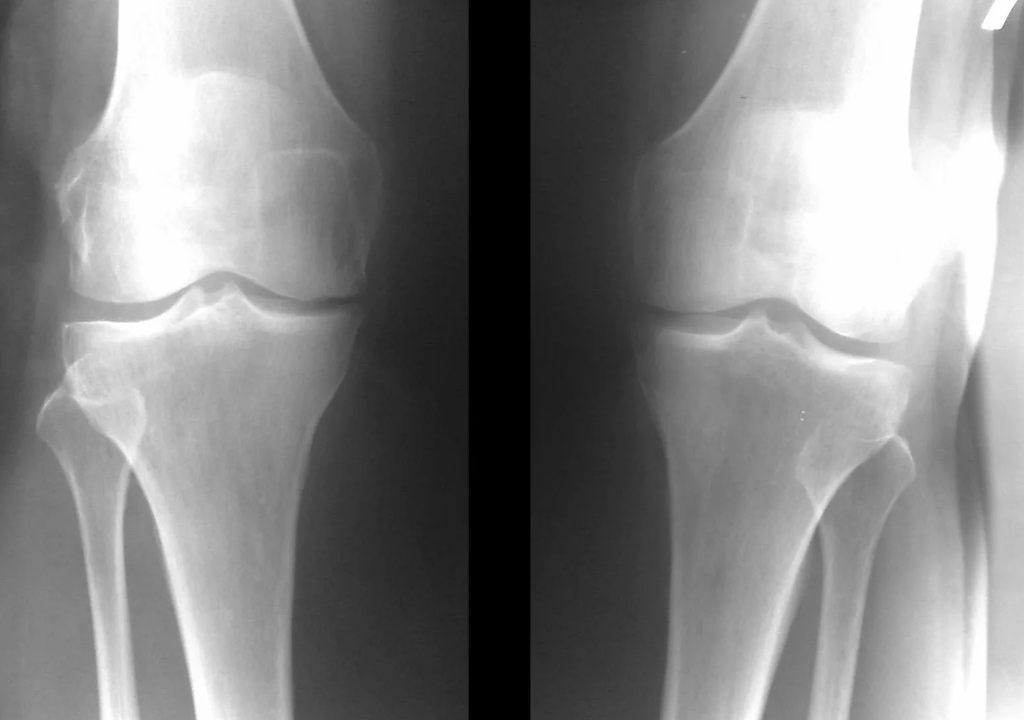

Στη συντριπτική πλειοψηφία των περιπτώσεων αρκεί η εξέταση και η ακτινογραφία της άρθρωσης του γόνατος σε δύο προεξοχές (άμεσες και πλάγιες). Τα κλινικά δεδομένα και οι εικόνες βοηθούν στον προσδιορισμό του σταδίου της νόσου.

διάγνωση της αρθρώσεως της άρθρωσης του γόνατος

Στα αρχικά στάδια της νόσου, με μικρές αλλαγές στον οστικό ιστό, η ακτινογραφία δεν είναι τόσο πολύτιμη. Σε αυτό το στάδιο, η γονάρθρωση μπορεί να διαγνωστεί μέσω αρθροσκόπησης. Η ακρίβεια της μεθόδου είναι πολύ υψηλή. μόνο η επεμβατική φύση και η τιμή του μπορούν να το σταματήσουν.